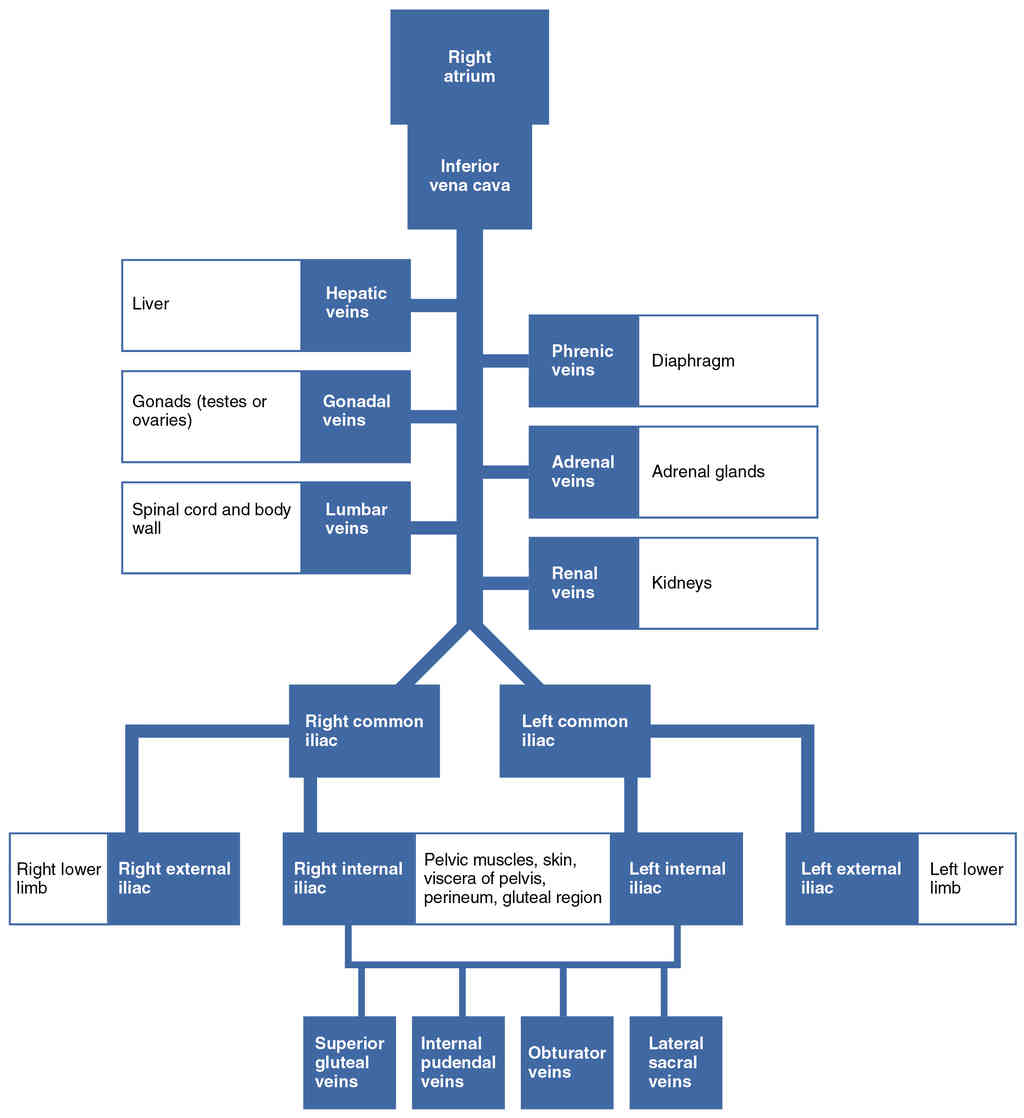

This page is under construction. For now, it is just a resource of the images found in the OpenStax Anatomy and Physiology Handbook. It wil slowly change into a revision tool. Each slide has a number. Use this to refer to the slide. When completed, it will have an unlabelled section, with labelled slides in parallel. On the unlabelled slides, write your answer and use the labelled slide to assess yourself. Keep track by also noting the number on each slide. Improvement at each attempt is important, more so than full marks on a first attempt.